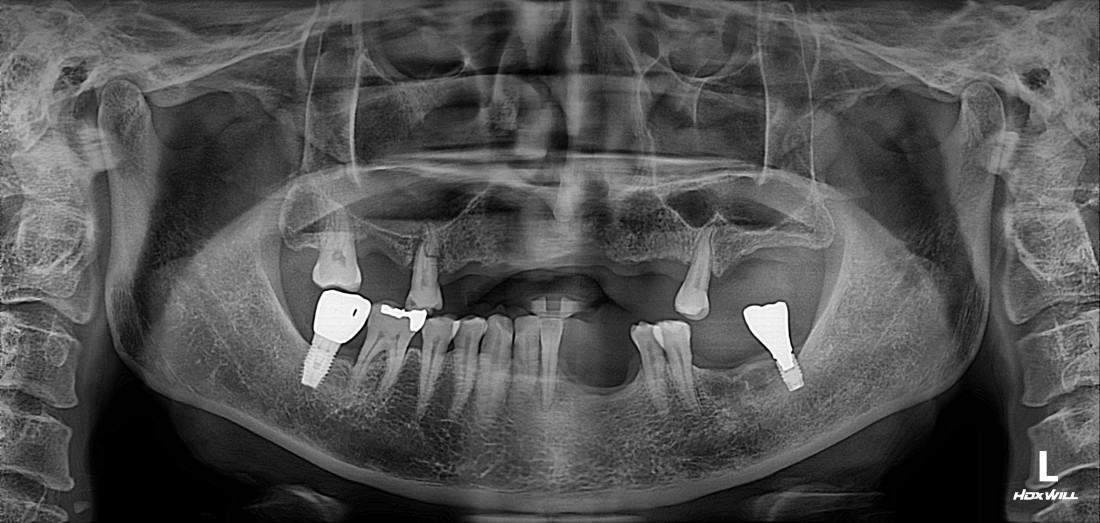

전남광주 임플란트는

붓기, 통증, 출혈을 줄인

구강외과 전문의의

디지털가이드 임플란트로

전남광주 임플란트치과에서는

경험많은 구강외과 전문의 진료로

디지털가이드 임플란트 수술을

진행하고 있습니다.

자동차가 네비게이션을 따라

정확한 목적지에 도착하듯,

디지털 가이드 임플란트를 통해

미리 가이드를 제작하기 때문에

정확한 위치에 정확한 깊이로

전남광주 임플란트를 식립할 수 있습니다.